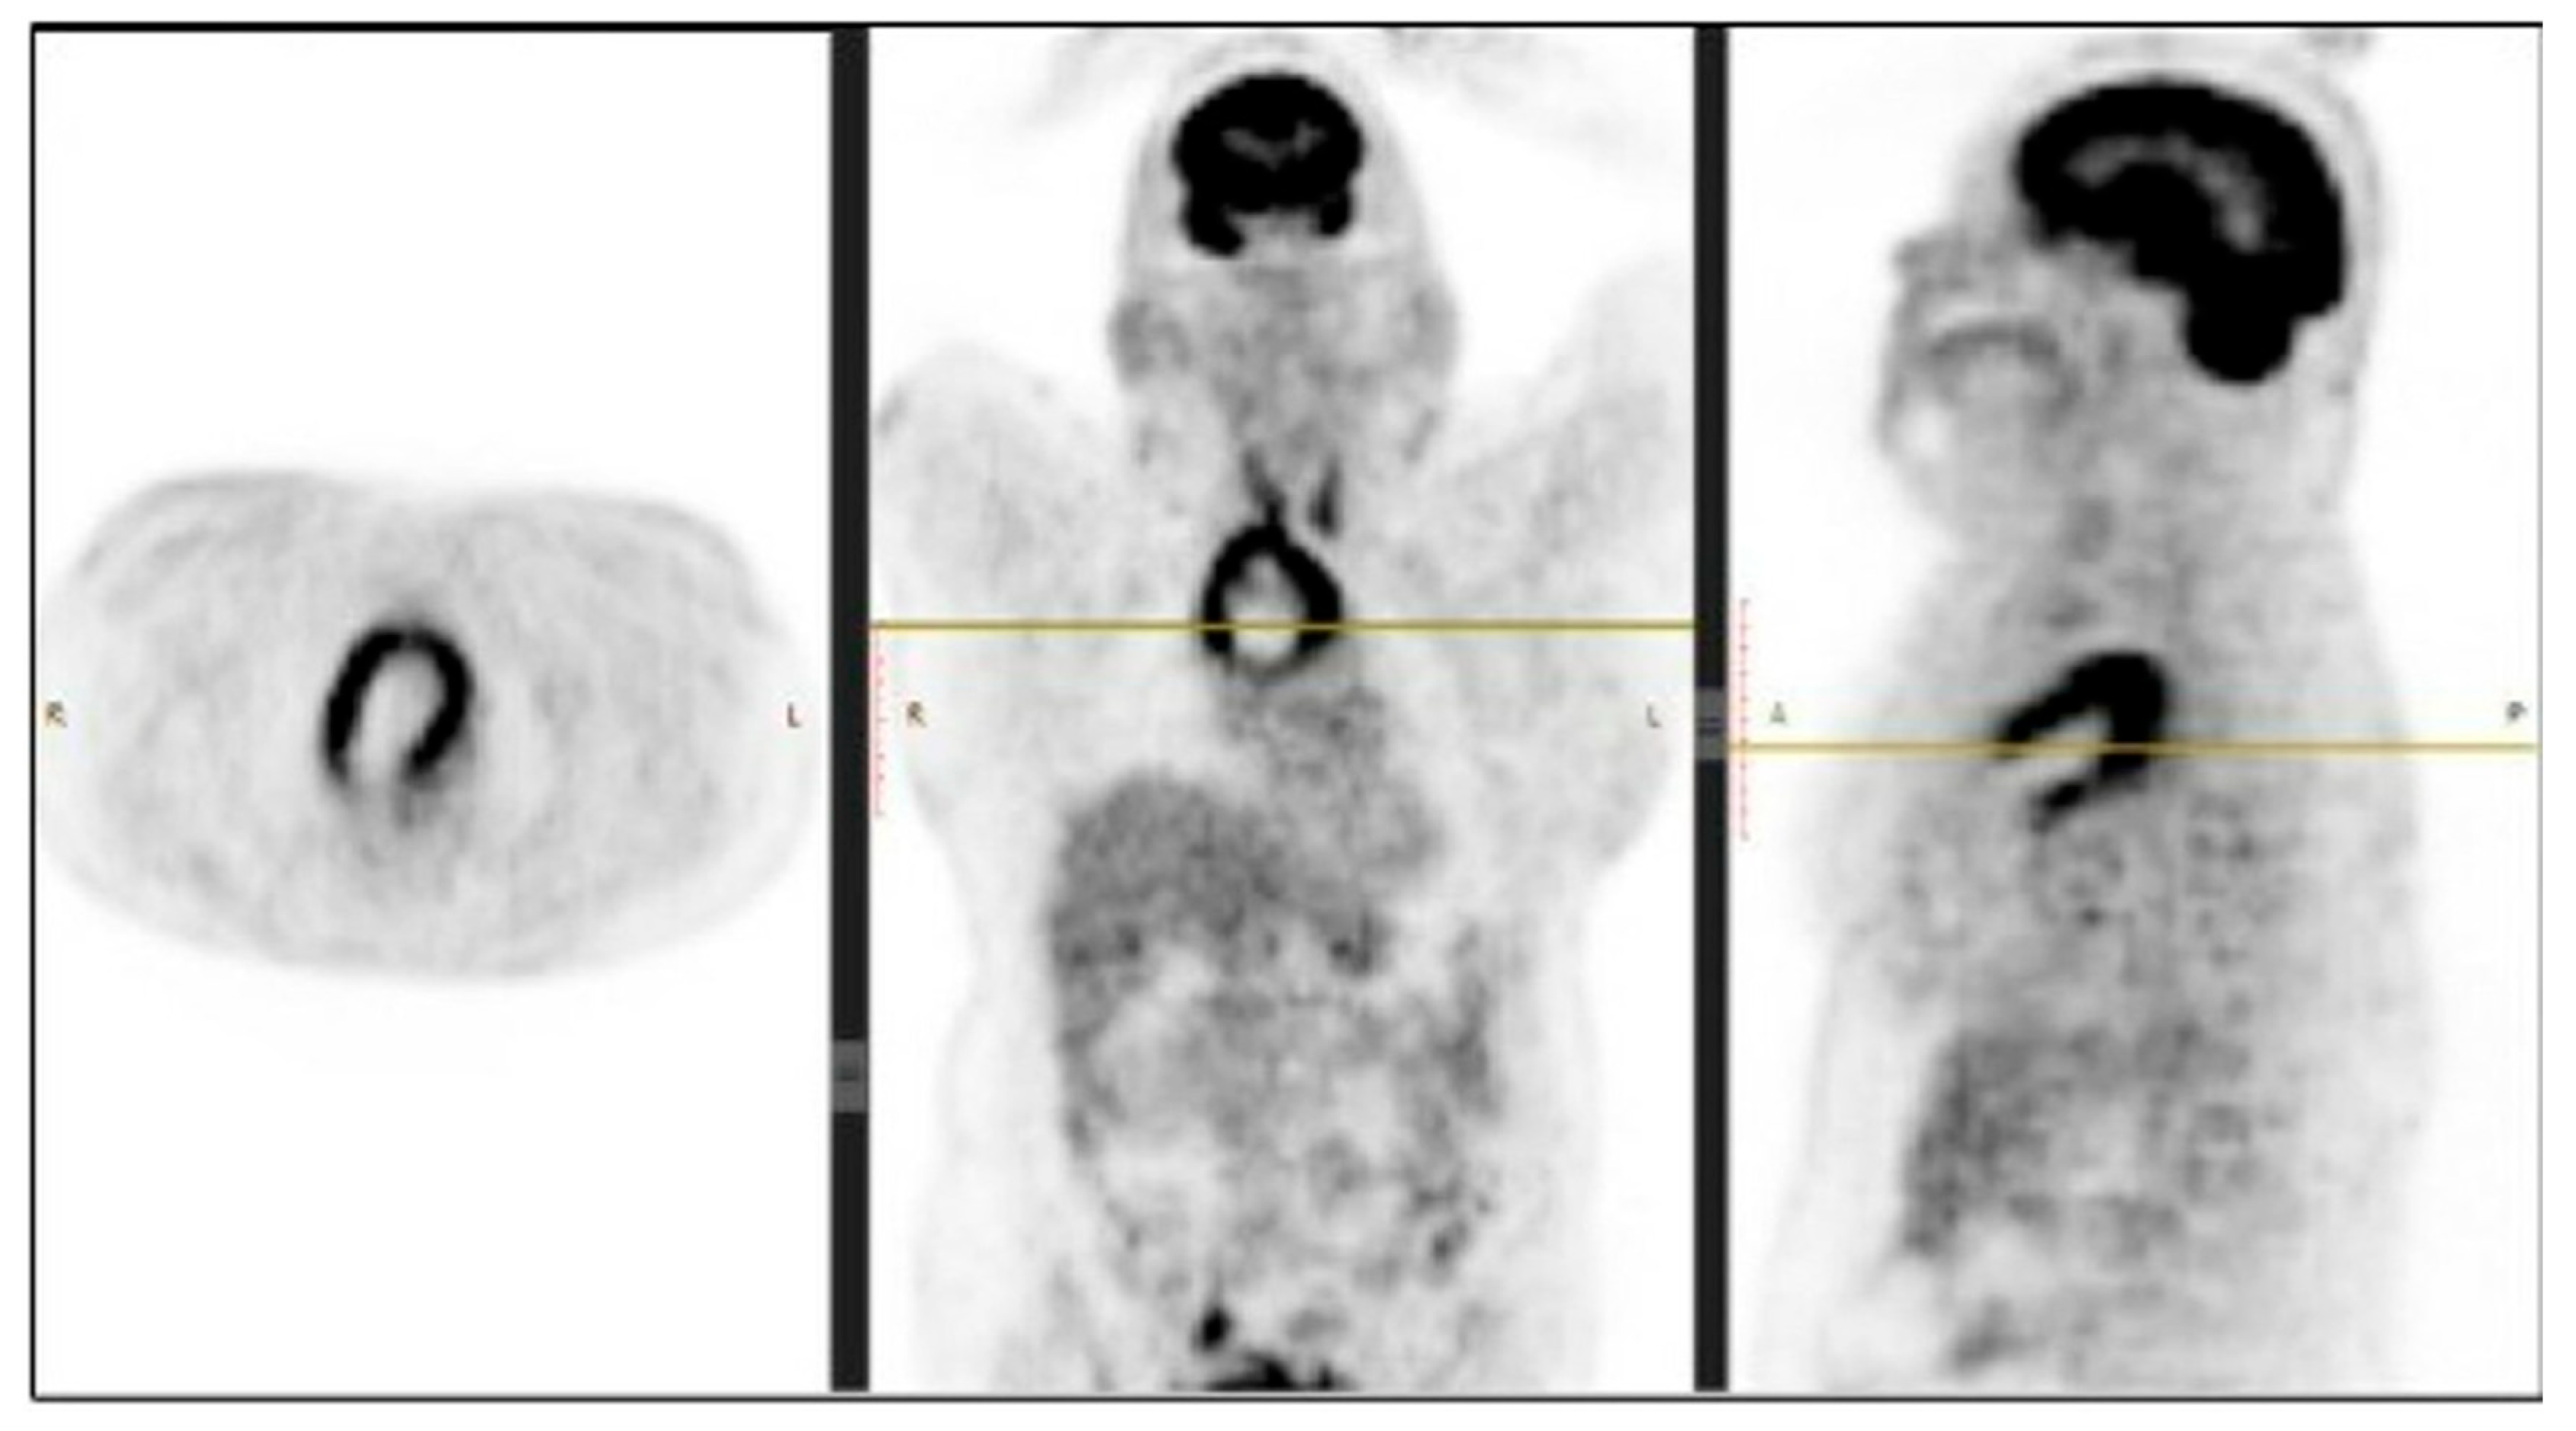

The performed contrast-enhanced computerised tomography (CECT) of the chest revealed a large, well-defined, centrally necrotic, peripherally enhancing mass lesion in the superior mediastinum extending to the anterior mediastinum. There was displacement of the trachea to the left side, compression of brachiocephalic veins and proximal SVC, and a possibility of sclerotic skeletal metastasis in the vertebrae (Figure 2). A CT-guided biopsy was planned, and a fluorodeoxyglucose (FDG) positron emission tomography (PET) scan (SUV-13.1) was performed to differentiate between a malignancy or a mass with an infective lesion and to look for metastasis. The scan revealed a large 10.7 × 6.5 × 6.2 cm well-defined mass lesion of neoplastic aetiology with a mass effect—likely of thymic origin, but with no evidence of metastasis (Figure 3).

Figure 3.

PET scan showing metabolic activity in the mediastinal mass. Abbreviations: R: Right; L: Left.